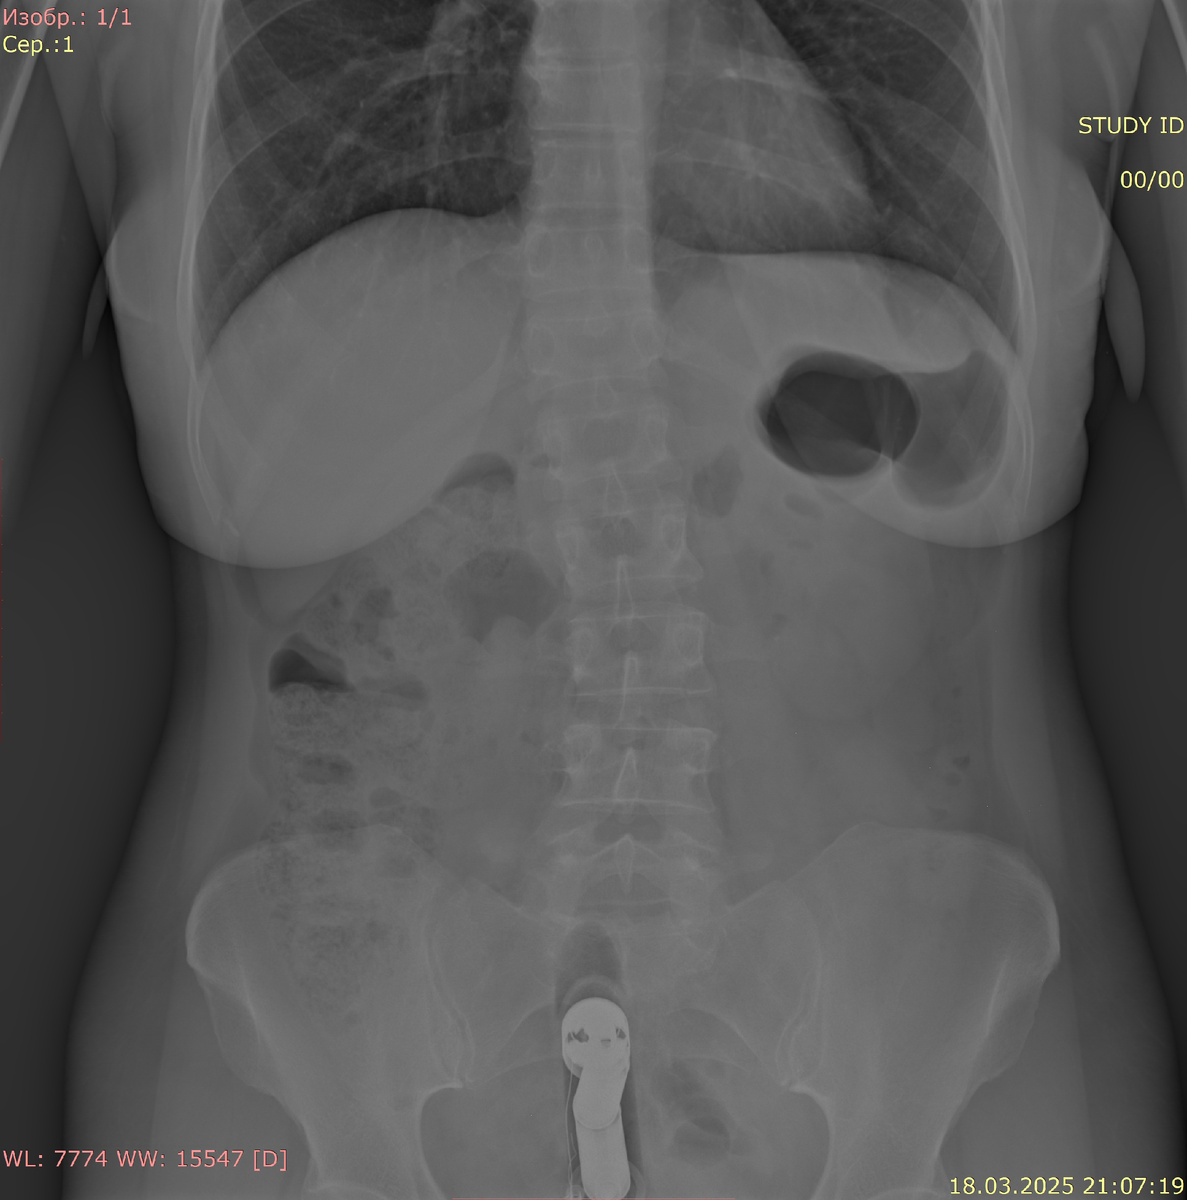

Рентгенография органов брюшной полости в прямой проекции:

В проекции прямой кишки цилиндрическое инородное тело до 7 см длиной. Кишечник умеренно пневматизирован. Патологических уровней газ-жидкость не определяется. Под куполами диафрагмы свободный газ не определяется.

Заключение: инородное тело в проекции прямой кишки. Данных за перфорацию полого органа и острую кишечную непроходимость не получено.